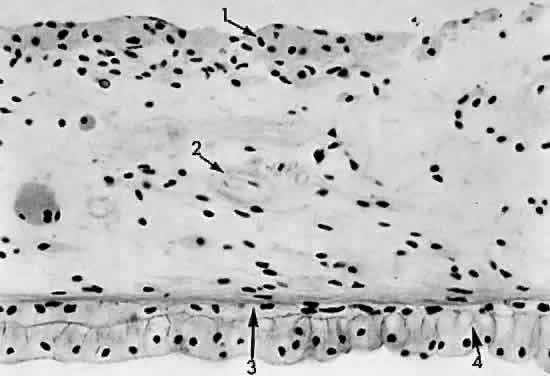

The pars plana is a 4-mm flat band area extending posterior to the ciliary processes. It joins with the peripheral cystoid retina at the ora serrata (Fig. 13). The nonpigmented epithelial layer flattens anteriorly but becomes columnar posteriorly as it approaches the retina. The pigmented epithelial layer of the pars plana continues as the pigmented epithelium of the retina. A ridged cuticular layer (the reticulum of Muller) lying adjacent to the pigmented epithelium layer of Bruch's membrane at the ora serrata is an avascular connective tissue that separates the inner cuticular layer from the outer elastic layer of Bruch's membrane in the pars plana region (Fig. 14).

Fig. 13. Pars plana adjoining the retina at the ora serrata: 1, peripheral cystic retina; 2, ora serrata; 3, nonpigmented pars plana epithelium; 4, choroid; 5, sclera (× 225, KEI 8982B).

Fig. 14. Pars plana: 1, nonpigmented epithelium; 2, pigmented epithelium; 3, cuticular layer of Bruch's membrane; 4, avascular connective tissue layer; 5, elastic layer of Bruch's membrane; 6, vascular layer of pars plana (× 225, KEI 8982B).

The nonpigmented epithelium of the pars plana secretes the acid mucopolysaccharide component of the vitreous body at its basal attachment. The lens zonules are firmly attached to the nonpigmented epithelial cells of the pars plicata, so that during cataract surgery traction may cause detachment of the nonpigmented epithelium if the zonules are broken.